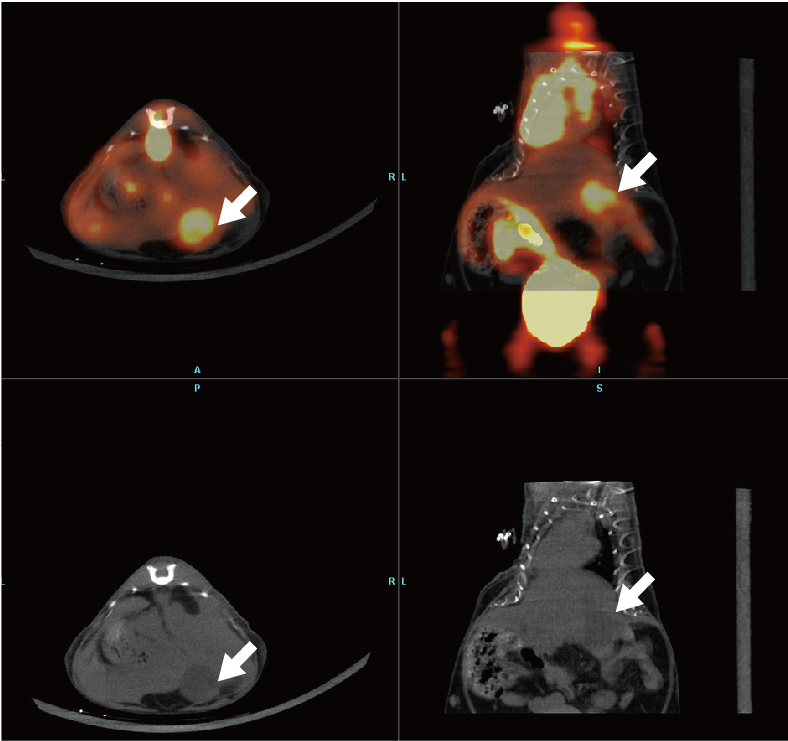

如图:为18F-FDG在原位肝癌中Micro-PET显像,下图为CT扫描出的原位肝癌显像,白色箭头所指部位为肿瘤。